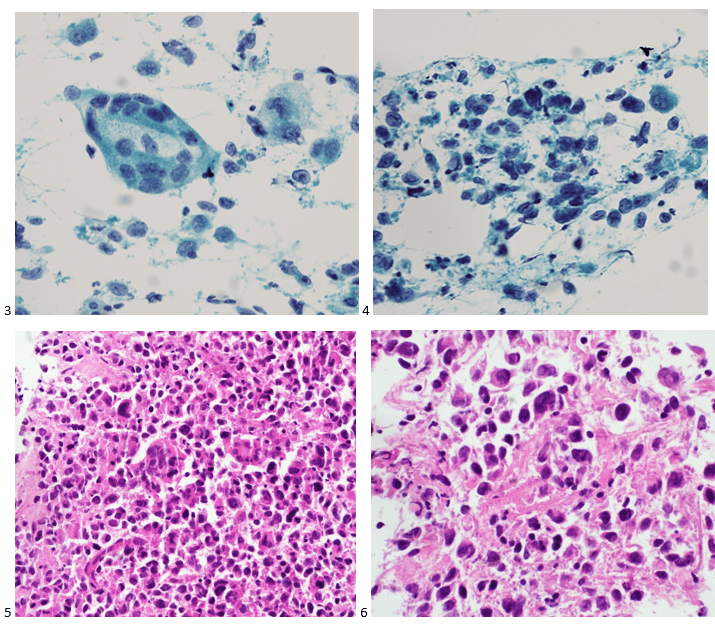

Case 2. Lung, Left Lower Lobe, CT-guided FNA

A 72-year old male with stage IIA squamous cell carcinoma underwent a VATS right upper lobectomy and mediastinal lymph node dissection. He completed adjuvant carboplatin/gemcitabine therapy. On a surveillance CT scan, the treated area demonstrated progression as well as multiple bilateral lung nodules. To determine whether the new left lower lobe superior segment lung nodule was a metastasis or new primary, a CT-guided biopsy was performed. The smears and cell block sections were negative for malignancy but demonstrated inflammatory cells and necrotic debris, consistent with a necrotizing inflammatory process (Images 3-5). A separate pass was sent for microbiological cultures to correlate our findings. The following day, Kinyoun and GMS stains were performed on paraffin-embedded sections of the cell block. No fungal organisms were identified on GMS, but acid-fast bacilli were noted by the cytologist on the Kinyoun-stained section (Image 6).

Diagnosis: Acid-fast bacilli (AFB), consistent with Mycobacterium Avium Complex. Isolated and confirmed by microbiology.